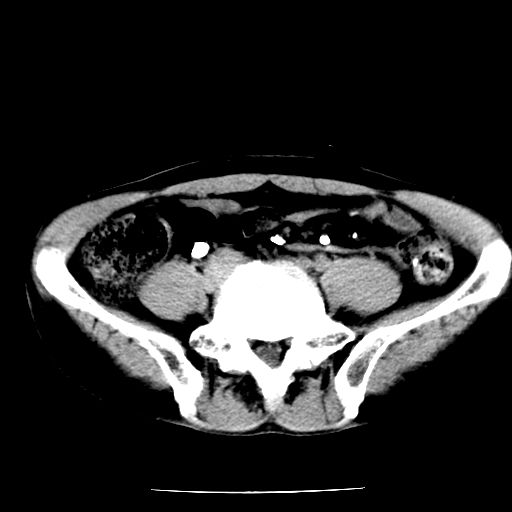

男,59岁,“结核性胸膜炎”30余年,胸部经常疼痛,多次x检查提示“肺部”炎症。腹部疼痛5日,b超提示:“肝内短管结石,余显示不清,建议进一步检查。”

两肺结核并右侧胸腔积液;脾脏、腹腔及腹膜后淋巴结结核[陈旧性];肝内胆管结石

胸部腹部都是结核(双肺。纵隔淋巴结,肝脏,脾脏,肠系膜)

两肺结核并右侧胸腔积液;脾脏、腹腔及腹膜后淋巴结结核[陈旧性];肝内胆管结石。直肠息肉?